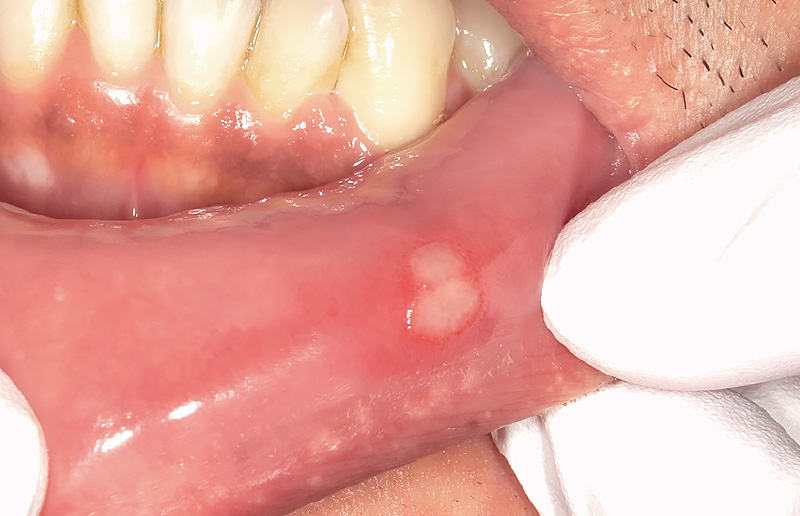

![[写真] 誤咬による舌口内炎](/academic/dentalmagazine/wp-content/uploads/sites/2/2026/04//196-8_photo04.jpg)

図4 誤咬による舌口内炎 -